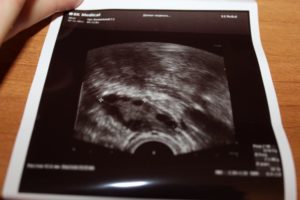

Очень волнительный момент – наступление ожидаемой беременности. Три дня задержки, две полоски на тесте, купленном в ближайшем супермаркете, и женщина уже уверена, что желанное зачатие осуществилось. Однако для точного подтверждения этого факта, а также чтобы убедиться, что плодное яйцо, из которого вырастет будущий малыш, находится именно там, где должно, необходимо сделать УЗИ матки.

Женщина обращается к своему гинекологу, тот назначает ультразвуковую диагностику, но по итогам в заключении указано, что результат отрицательный: на УЗИ раннюю беременность не видно. Иногда бывает так, что и через месяц или чуть больше после положительного теста, УЗИ беременность не покажет. Почему так случается?

В первые недели развития эмбриона имеет смысл выполнять только трансвагинальное УЗИ.

Это обследование предполагает, что датчик вытянутой формы небольшого диаметра вводят во влагалище женщины и получают с его помощью изображение матки на мониторе аппарата.

В связи с тем, что датчик максимально приближен к изучаемой зоне, тонность исследования очень высокая. Специфической подготовки такое УЗИ не требует. Оно безопасно и не приносит осложнений.